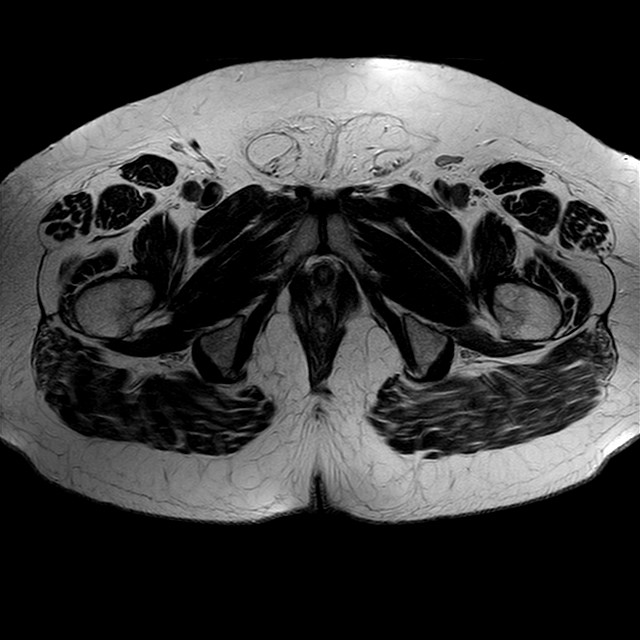

Esami: RMN BACINO

eT2w TSE

Evidenti e simmetriche alterazioni osteofitosiche in regione coxo femorale con riduzione delle rime articolari. Degenerazione completa del cercine glenoideo. Non attuali segni di versamento articolare. Non segni di edema osseo che escludono attuale algodistrofia od osteonecrosi. Lieve e simmetrica riduzione del trofismo della muscolatura glutea.